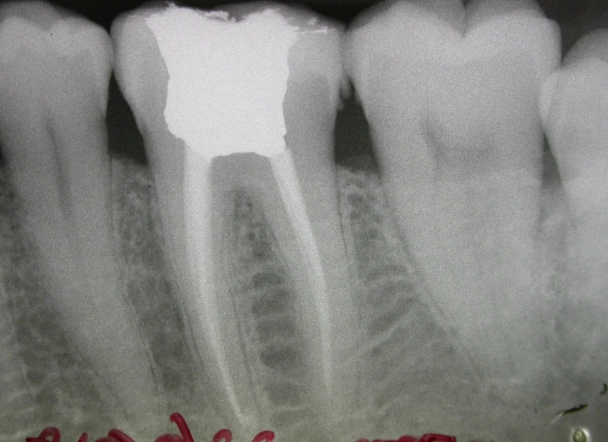

- More Roots and Canals: Front teeth might have one root. A molar can have two, three, or even four roots, each with one or more canals. Finding and cleaning all of them is a precise task.

- Complex Anatomy: The canals inside molar roots can be curved, narrow, or branch out in unexpected ways. It's like cleaning a intricate, microscopic cave system.

After the canals are cleaned, shaped, and dried, they need to be filled to prevent re-infection. A biocompatible material, usually a rubber-like substance called gutta-percha, is used to fill the space. It's sealed in place with a dental adhesive cement. The goal is to hermetically seal the root canal system.

- Missed Canals: Remember those complex molar anatomy? Sometimes a tiny, extra canal is missed during cleaning and remains infected.

- Incomplete Cleaning: Severely curved or blocked canals might not be fully cleaned.

- Poor Seal: If the filling material doesn't seal the tip of the root perfectly, bacteria can leak back in.

Signs of a failing root canal are similar to the original problem: pain, swelling, a recurring pimple on the gum (sinus tract), or sometimes it's only visible on a follow-up X-ray.